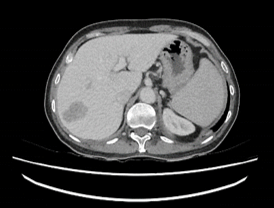

Figure 2B: Venous phase of computed tomography scan of the liver, the lesion in segment VII remain hypodense relative to liver.

We proceeded with a computed tomography of the liver (CT liver) for further evaluation. CT liver showed a 4.3 x 2.4cm heterogeneously hypodense lobulated mass in segment VII of the liver. The mass was hypodense to the liver on all phases (plain, arterial, venous and delayed). There was mild heterogeneous enhancement, but there was no arterial enhancement (Figure 2A), washout (Figures 2B & 2C) or pseudo capsule, which should be expected in hepatocellular carcinoma. In view of the known history of thalassemia and the presence of paravertebral soft tissue masses that were likely to be extramedullary haematopoiesis, the possibility of extramedullary haematopoiesis was suggested. The other lesion was a 0.9cm hypodensity in segment VI of the liver, which was diagnosed as a flash-filling haemangioma. A magnetic resonance imaging (MRI) was then ordered for the indeterminate segment VII lesion. On MRI, the hepatic segment VII mass in question showed mild heterogeneous contrast enhancement but no appreciable arterial enhancement, washout or pseudo capsule (Figure 3A & Figure 3B).